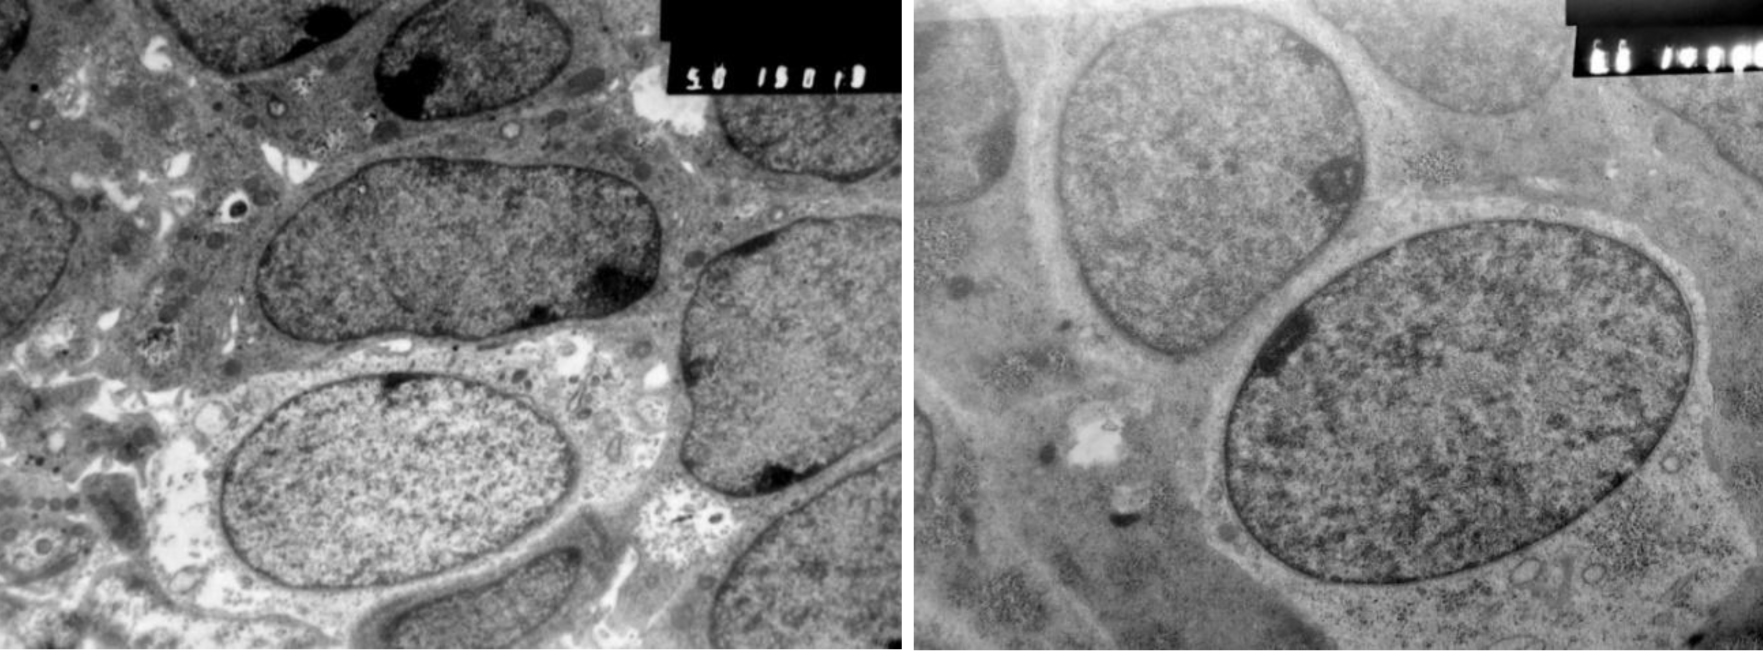

Карман Сесселя в гистологическом препарате ограничивает нарастающий пласт многослойного эпителия, который смещается с задней стенки КР на дорзальную стенку глоточной кишки. Перемещение многорядного эпителия по градиенту роста КР сопровождается активизацией апоптоза, пролиферацией клеток в составе пласта и мезенхиме, а также формированием эпителиоцитов качественно новой генерации, потерявших связь с базальной пластинкой эпителия и участвующих в восполнении дефектов в нишах апоптоза (рис. 4).

Рис. 4. Эмбрион человека. Биологический возраст 44–46 суток. Зона перехода стомодеального эпителия в карман Ратке. Стрелки – участок с апоптозом эпителия, МК – мезенхимальные клетки, ЭК – эпителиальные клетки стомодеума. Электроннограмма, ув. ×4000. Шкала – 10 мкм